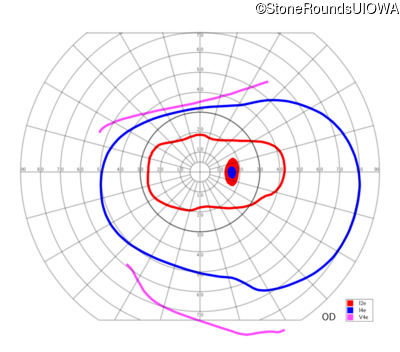

| OD | OS | ||

|---|---|---|---|